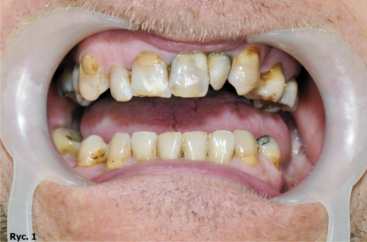

Pacjent B.J., lat 45, zgłosił się do gabinetu w celu poprawy estetyki i uzupełnienia braków zębowych. W badaniu zewnątrzustnym zaobserwowano wysunięcie bródki, wygładzenie bruzdy bródkowo wargowej, pacjent miał charakterystyczne wzmożone napięcie warg i kłopoty z wymową niektórych głosek. W badaniu wewnątrzustnym stwierdzono odwrotne zachodzenie zębów siecznych, zęby ustawione w III klasie Angle’a. Wynik dodatni testu czynnościowego bez poprawy rysów twarzy pozwolił postawić rozpoznanie: przodozgryz całkowity (ryc. 1, 2, 3).